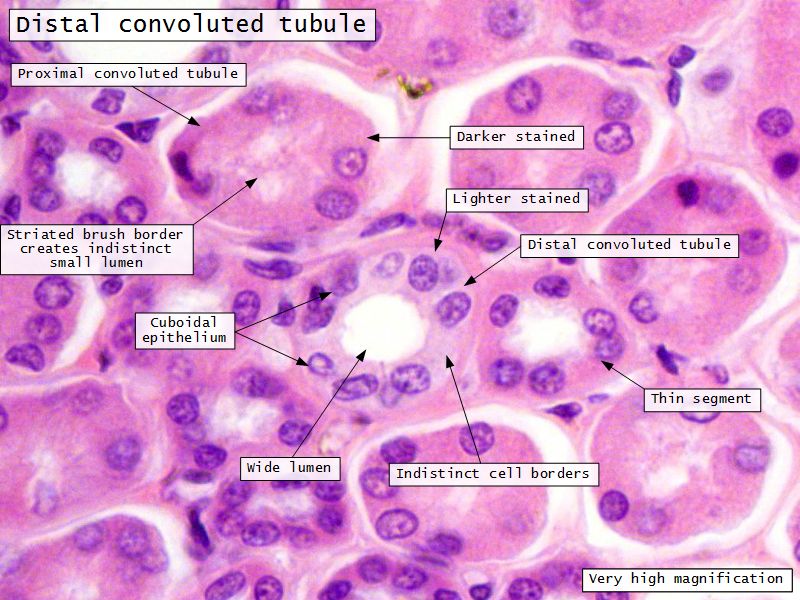

Proximal convoluted segment

- Longest part of nephron

- Wide triangular cell

- Spherical nucleus

- Indistinct cell borders

- Luminal surface

- Striated brush border

Loop of Henle - thin

- Narrow lumen

- Thin wall

- Squamous epithelium

- Looks like capillaries

Continuation of descending and ascending tubuliDistal convoluted tubuli

- Joins collecting tubule

- Cuboidal epithelium

- Light stained

- Wide looking lumen

- Indistinct borders